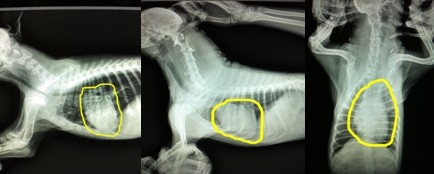

上圖中分享的依然是剛才的兩只犬的三張X光片,但是重點不一樣,通過圖片畫圈的位置可以發現,第一只犬是主要由于氣管狹窄,通氣不足引起的喘氣急促。第二張圖片,圖片中心臟的面積幾乎占了整個胸腔的一半,形狀也有明顯的異常,而氣管并沒有明顯異常影像,另外通過醫生的聽診和第三張不同體位的X光片的檢查分析,可確診此犬患有心臟病。X光片的確診對于心臟病十分重要,醫生會通過專業的測量和計算來判斷心臟病的類型和嚴重程度。